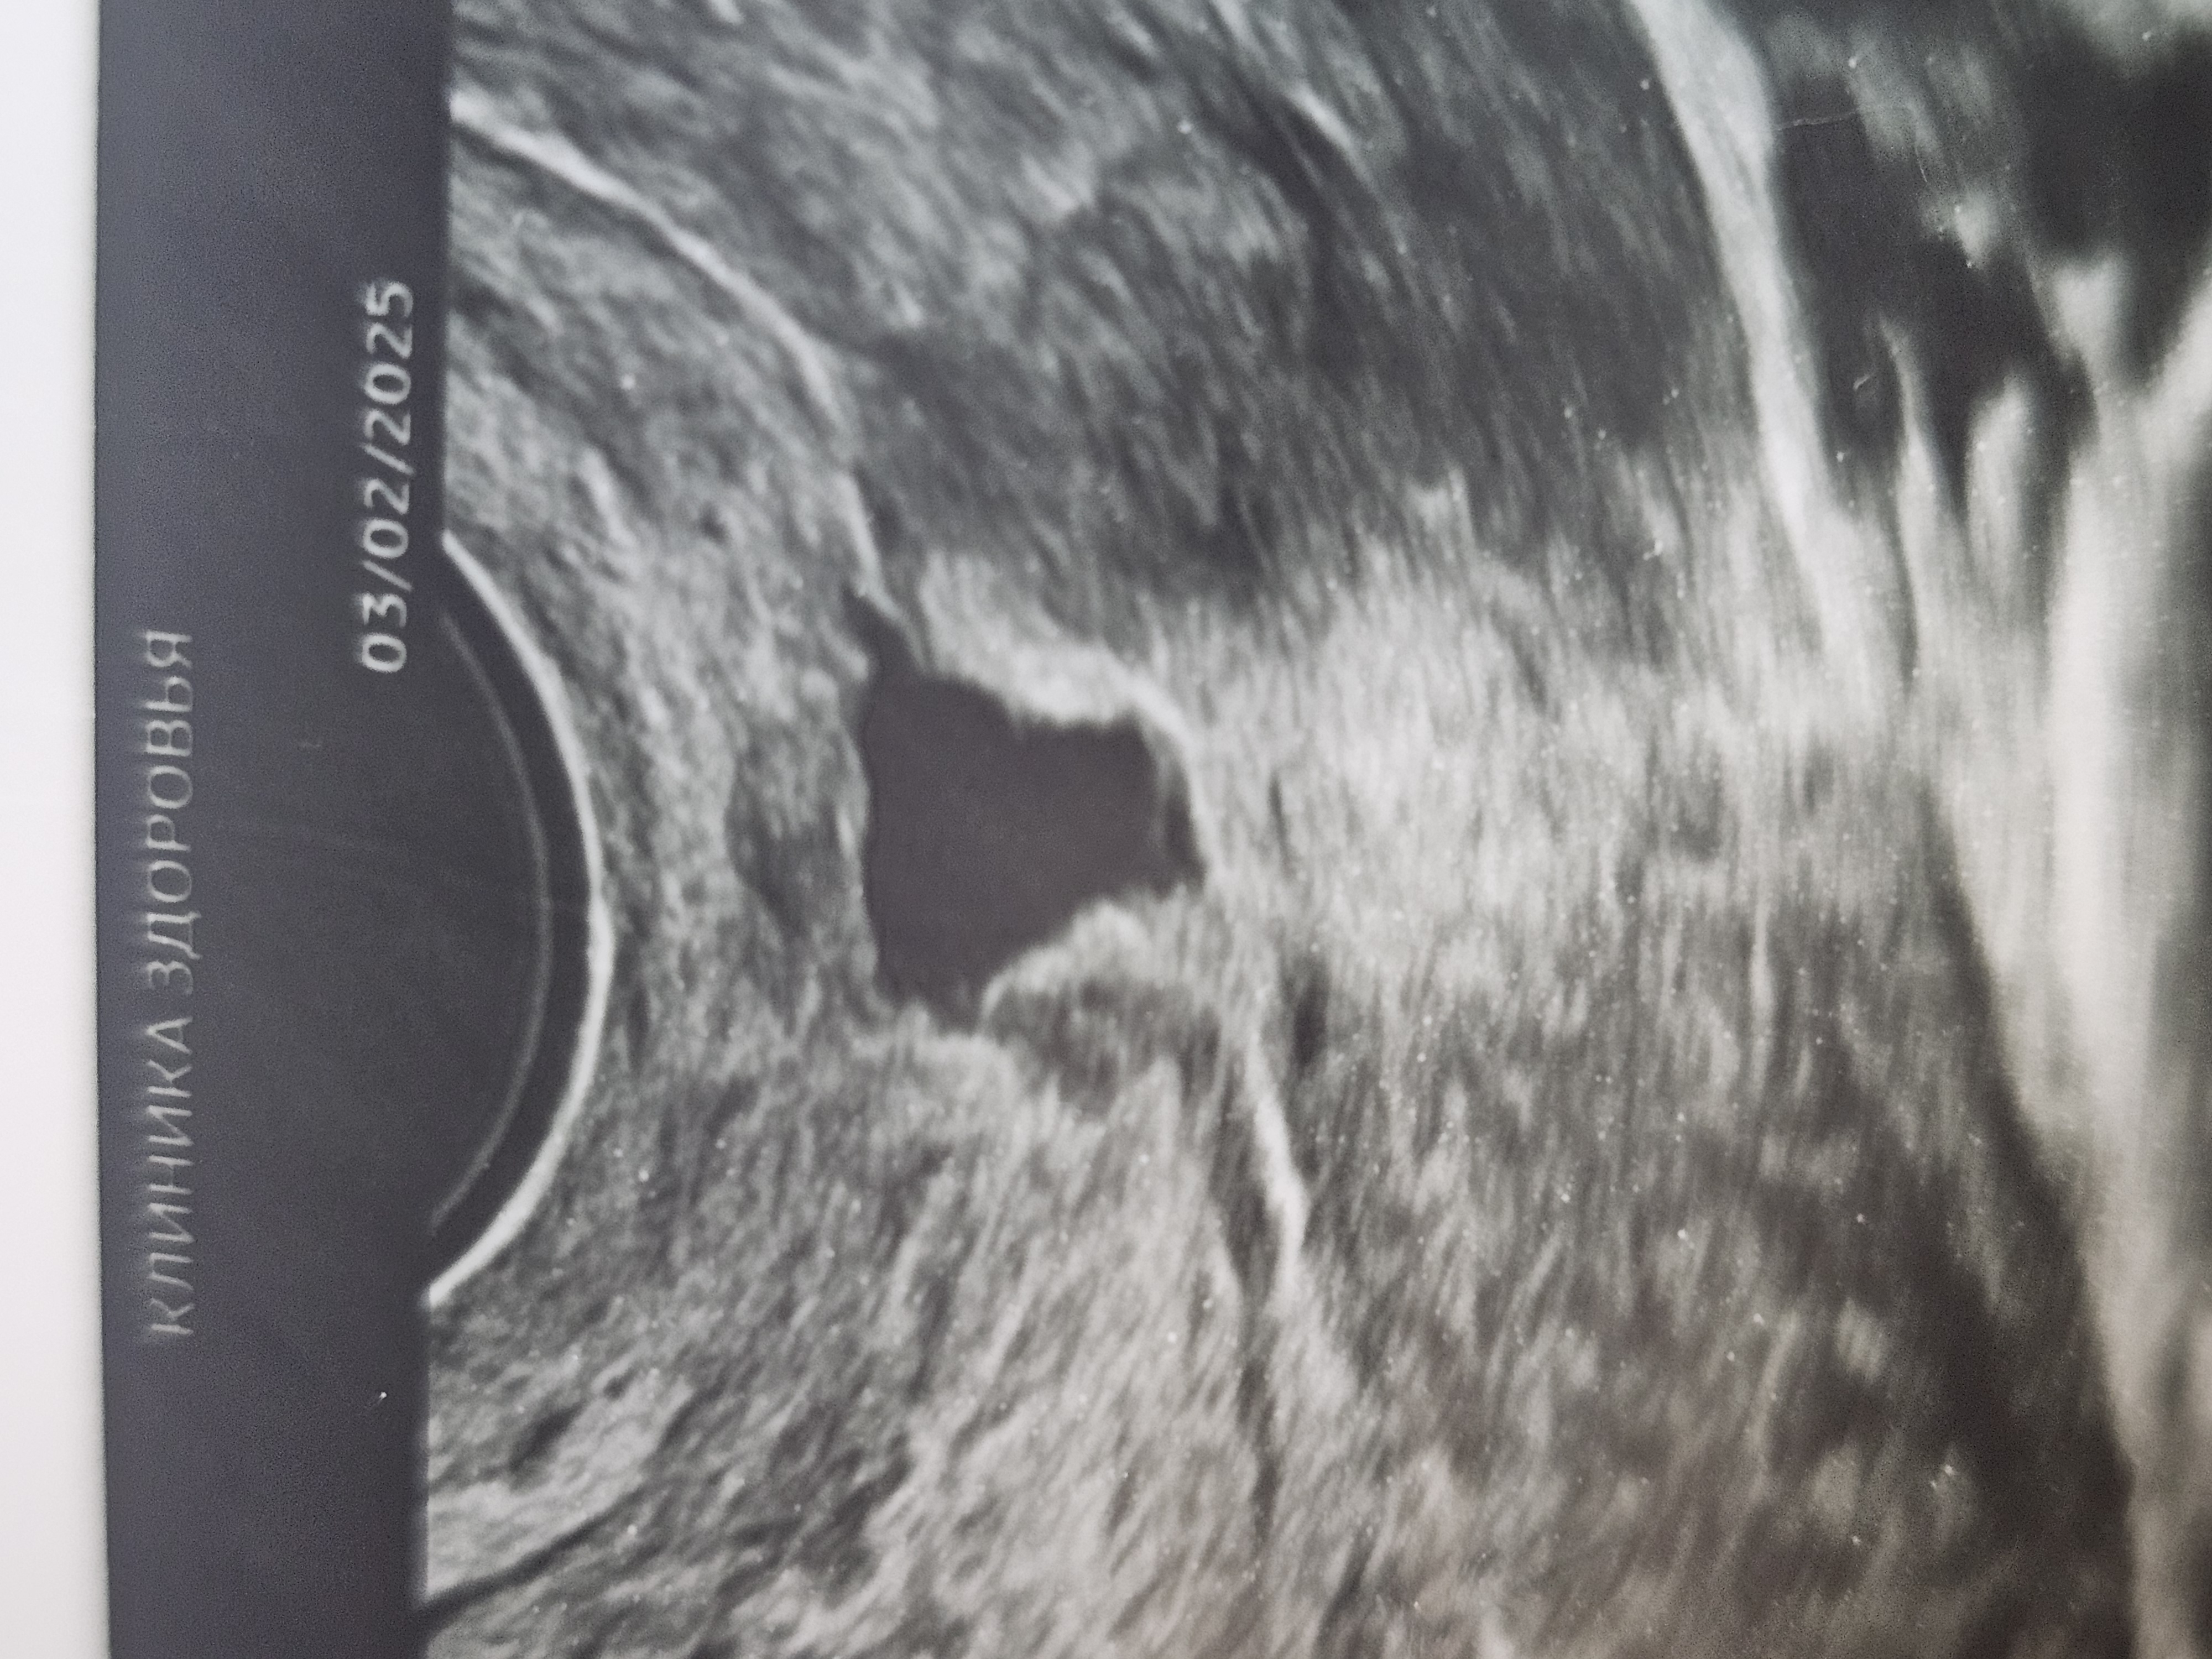

Результаты: УЗИ, КТГ, доплера, скринингаДелала узи на 12 дц. Врач утверждает, что это жт. Также в прошлом месяце у меня была приличная задержка , я думала, может, киста ? Врач говорит - ранняя о и жт. В яичниках мелкие фоллики на узи до 9 мм.

Овуляции ранней я не чувствовала, хотя всегда чувствовую (выделения и боли - прям в 100%).

Также на 17 дц - сильно тянуло низ и особенно левый яичник, немного бежевого. За несколько дней до 17 дц - выделения обильные, яичный белок. Вдруг это была овуляция? Тогда, что на узи??